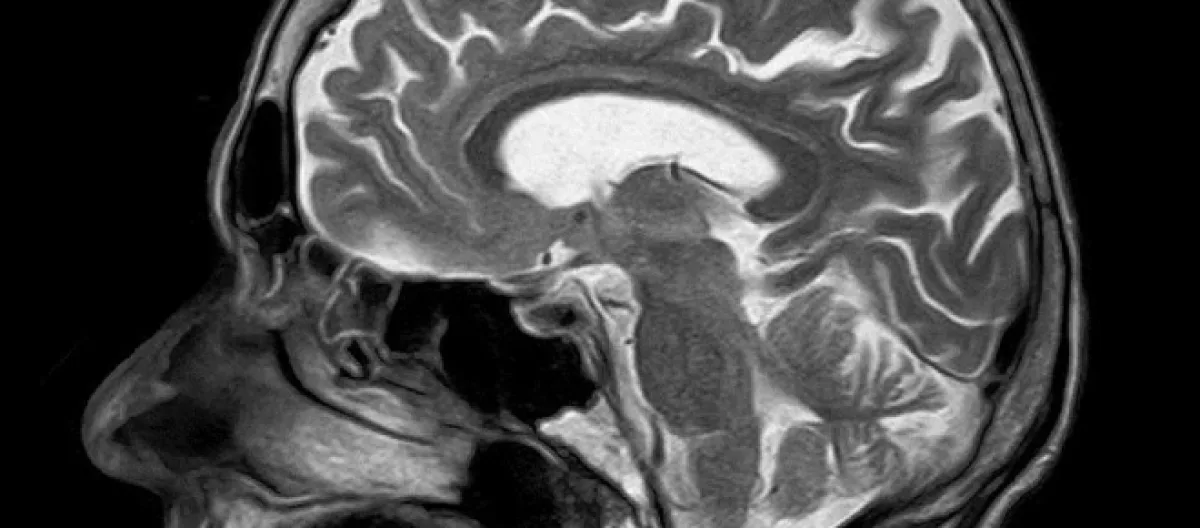

Se dice que una persona tiene un tumor en el cerebro cuando hay un incremento canceroso dentro del cerebro. El tumor maligno de un cáncer de cerebro afectará algunas funciones del cerebro, según el lugar donde se encuentre.